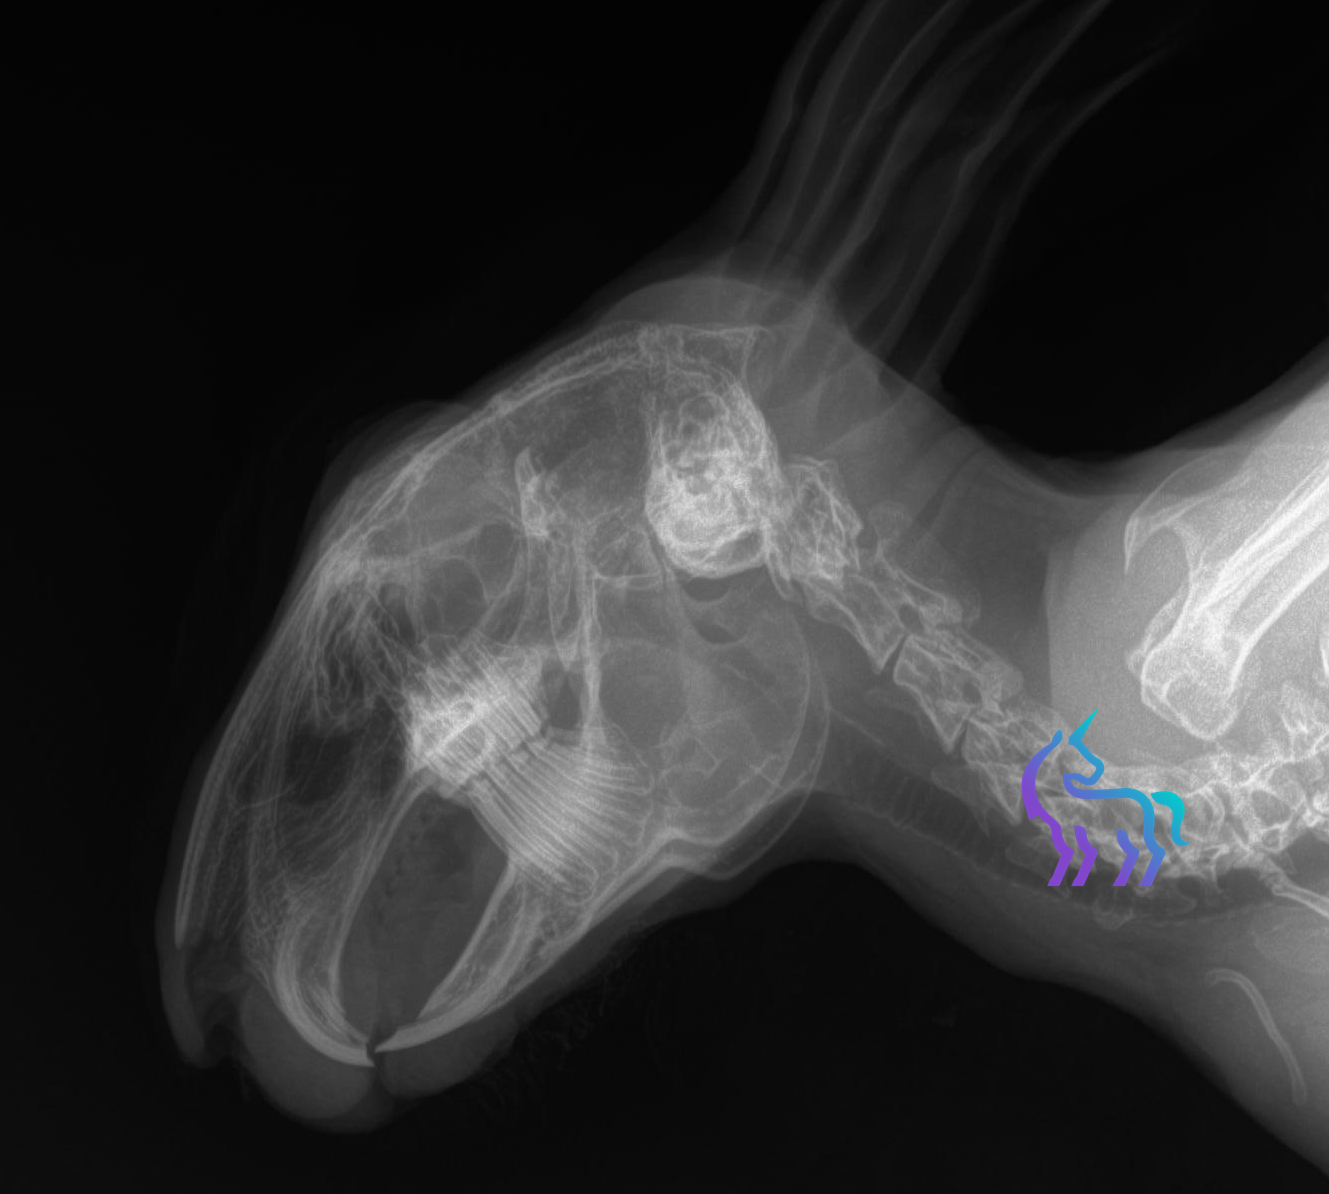

Radiographie mâchoire et sinus lapin

Proximité entre les racines dentaires et les sinus maxillaires.

Les racines des dents jugales maxillaires sont en proximité immédiate des sinus. Cette organisation explique pourquoi une maladie dentaire ou une atteinte du canal lacrymal sont si souvent à l’origine d’une rhinite persistante.